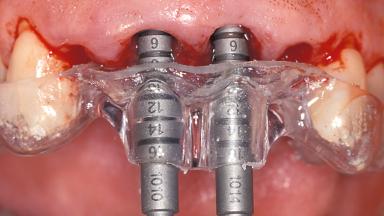

Replacement of the Four Maxillary Incisors with a Fixed Dental Prosthesis Using an Immediate Loading Protocol

In November 2001, a 53-year-old female presented seeking advice and options for treatment of her maxillary incisor teeth. She was dissatisfied with both the functional and esthetic qualities of her existing restorations. Her medical health was excellent, and she reported no contraindications to dental care. On presentation, the patient’s dental health was less than ideal. Although she had no probing depths greater than 3 mm, she suffered from generalized chronic adult periodontitis and displayed multiple sites of bleeding on probing. Her remaining dentition was heavily restored, and many teeth had been endodontically treated. Areas of recurrent dental caries were noted on many teeth. Radiographically and clinically, the maxillary incisor teeth exhibited large areas of active caries, and after the splinted crowns had been removed, the teeth were determined to be non-restorable.

# of Implants 2

Type of Implants One-Piece

Guided Surgery No